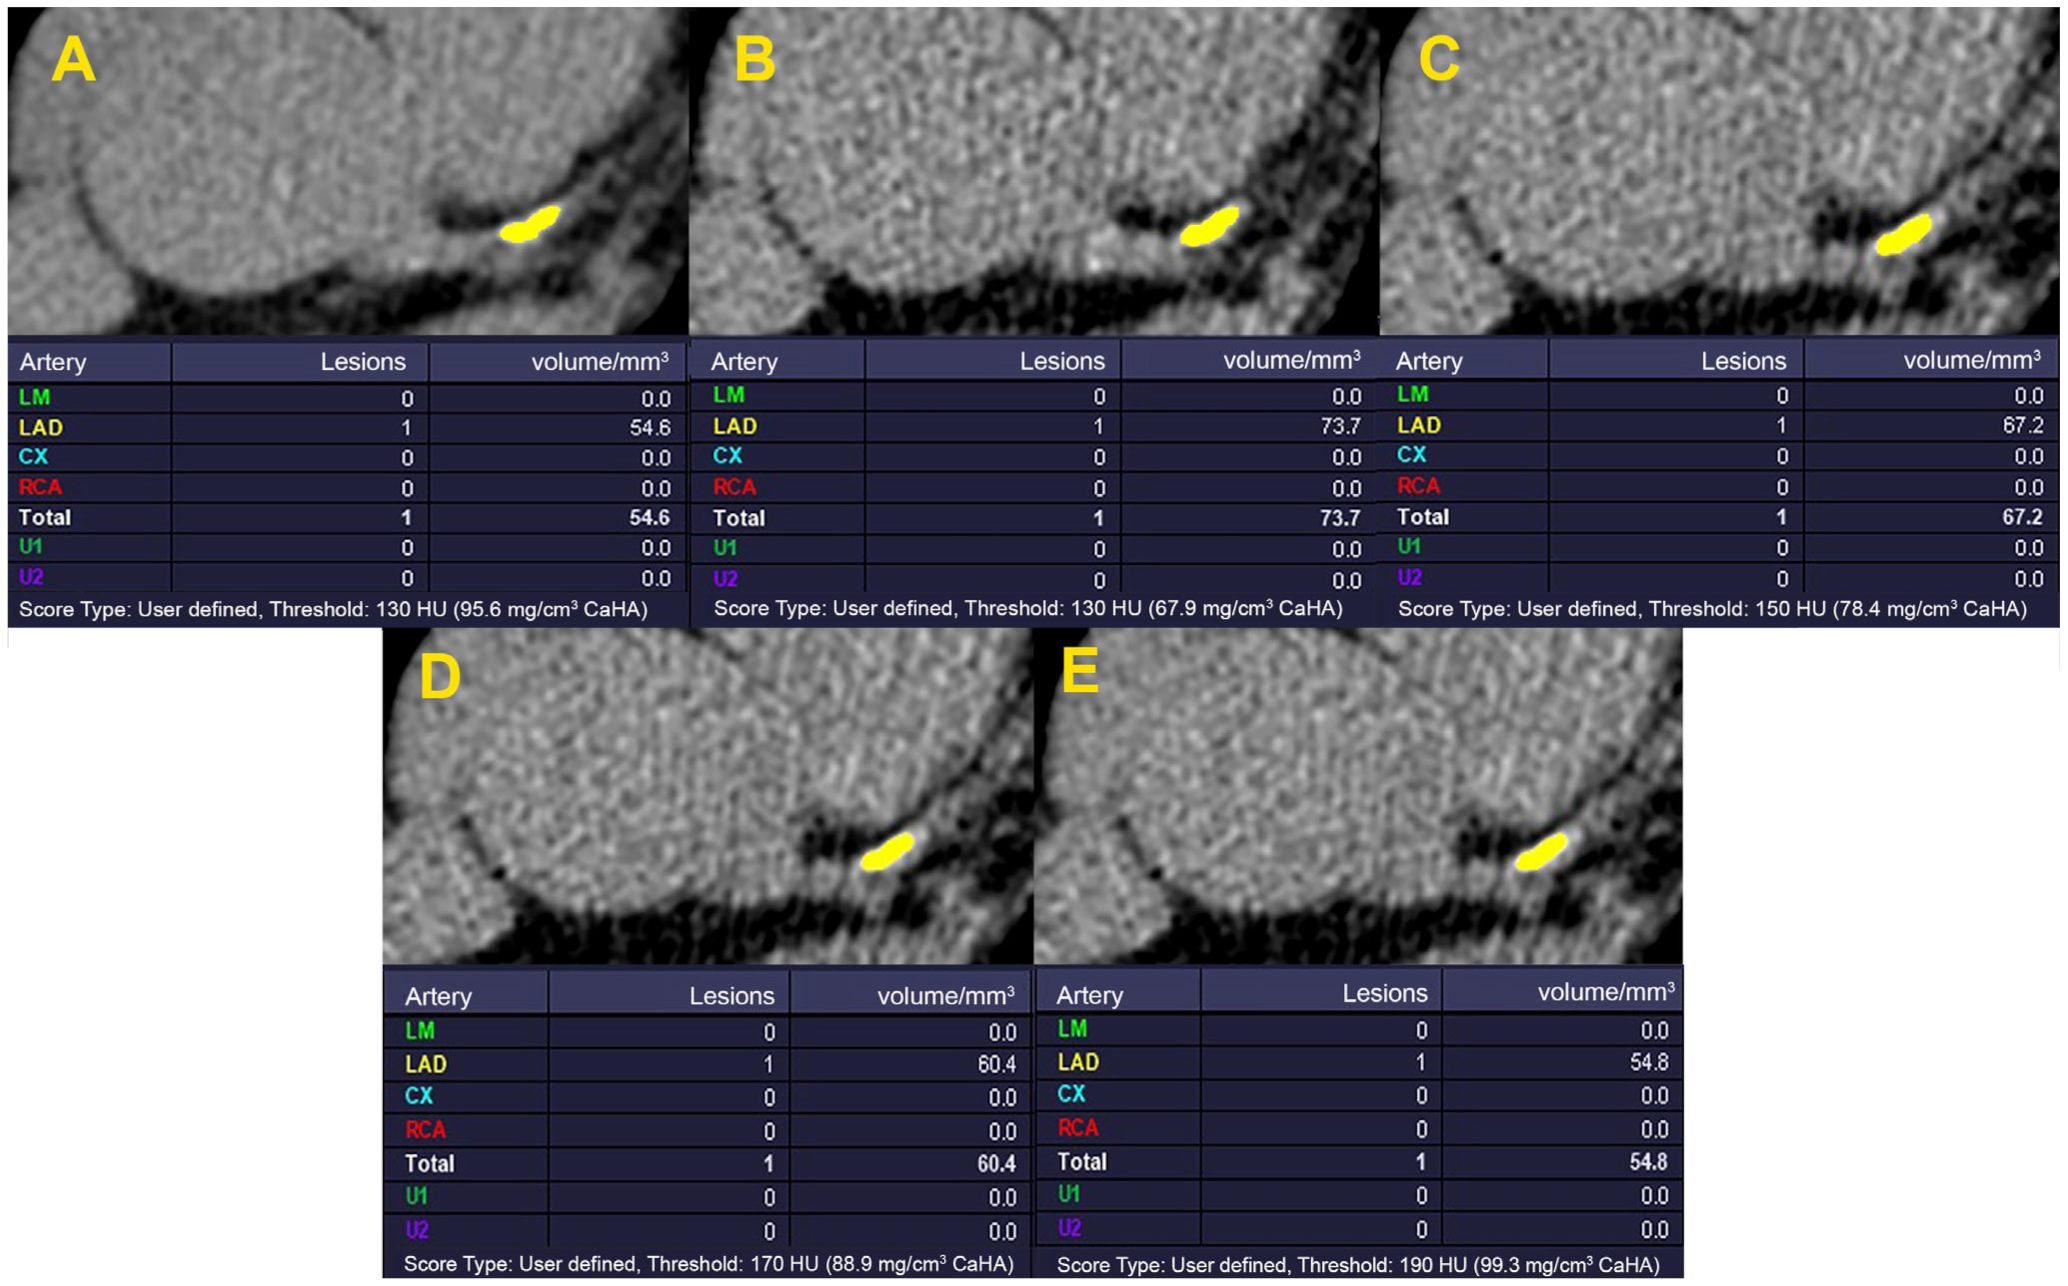

- Gräni, C.; Vontobel, J.; Benz, D.C.; Bacanovic, S.; Giannopoulos, A.A.; Messerli, M.; Grossmann, M.; Gebhard, C.; Pazhenkottil, A.P.; Gaemperli, O. Ultra-low-dose coronary artery calcium scoring using novel scoring thresholds for low tube voltage protocols—A pilot study. Eur. Heart J. -Cardiovasc. Imaging 2018, 19, 1362–1371. [Google Scholar] [CrossRef]